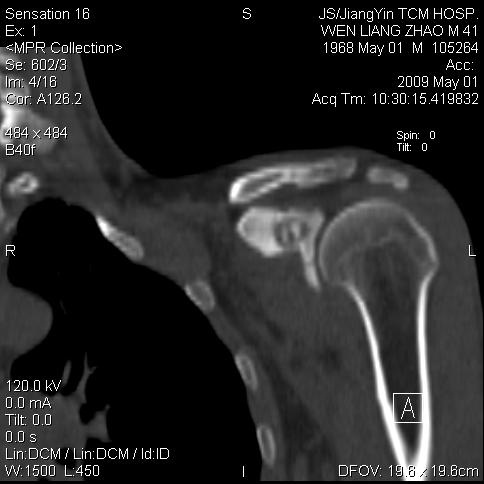

左侧喙突处压痛二年。考虑骨样骨瘤。

考虑骨样骨瘤,骨母细胞瘤待排。

病灶外缘膨胀明显,灶缘硬化较少,结合病史较符合骨母细胞瘤,其他亦不排除如软骨及软骨母细胞瘤等(病灶形态,成份较符合,发病部位也符合,只是年龄较大),骨样骨瘤多有较明显的自发性痛,且夜间痛明显,病史为压痛两年,不太符合.

多考虑内生性软骨瘤。年龄及发病部位及病史不支持骨样骨瘤。

支持骨样骨瘤(瘤巢小于1.5mm),骨母细胞瘤又称为巨大骨样骨瘤指瘤巢大于2cm的骨样骨瘤.

首先考虑内生软骨瘤,其次才考虑骨样骨瘤。